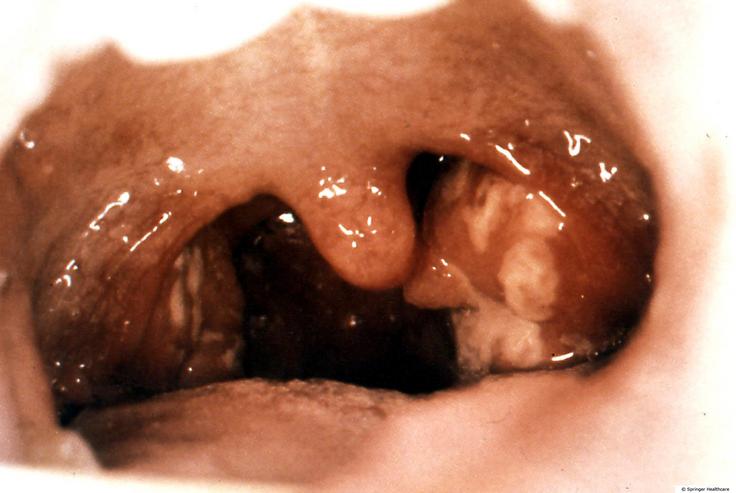

正常的扁桃体

化脓性扁桃体炎

慢性扁桃体炎,扁桃体肥大